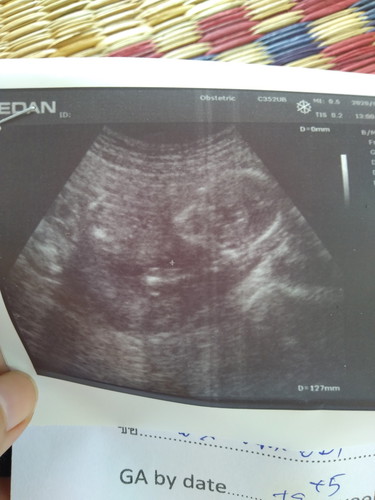

วันนี้ไปอุบลตร้าซาวน์ที่คลีนิคมาค่ะ ท้องได้19วีค5วัน แต่หมอบอกว่าเด็กตัวเล็กเท่าเด็ก17วีค5วันเองค่ะน้ำหนักไม่ขึ้นเลยค่ะ แล้วหัวใจเราก็เต้นเร็ว เราเลือดจางเสี่ยงเป็นทารัสซีเมีย และเสี่ยงเป็นไทรอย มีโอกาสที่เด็กออกมาแล้วจะเป็นเอ๋อ จากที่จะต้องคลอดประมาณต้นเดือนตุลาก็เลื่อนมาเป็น25ตุลา ทำยังไงได้บ้างค่ะท้องแรกกังวลมากเลยค่ะ